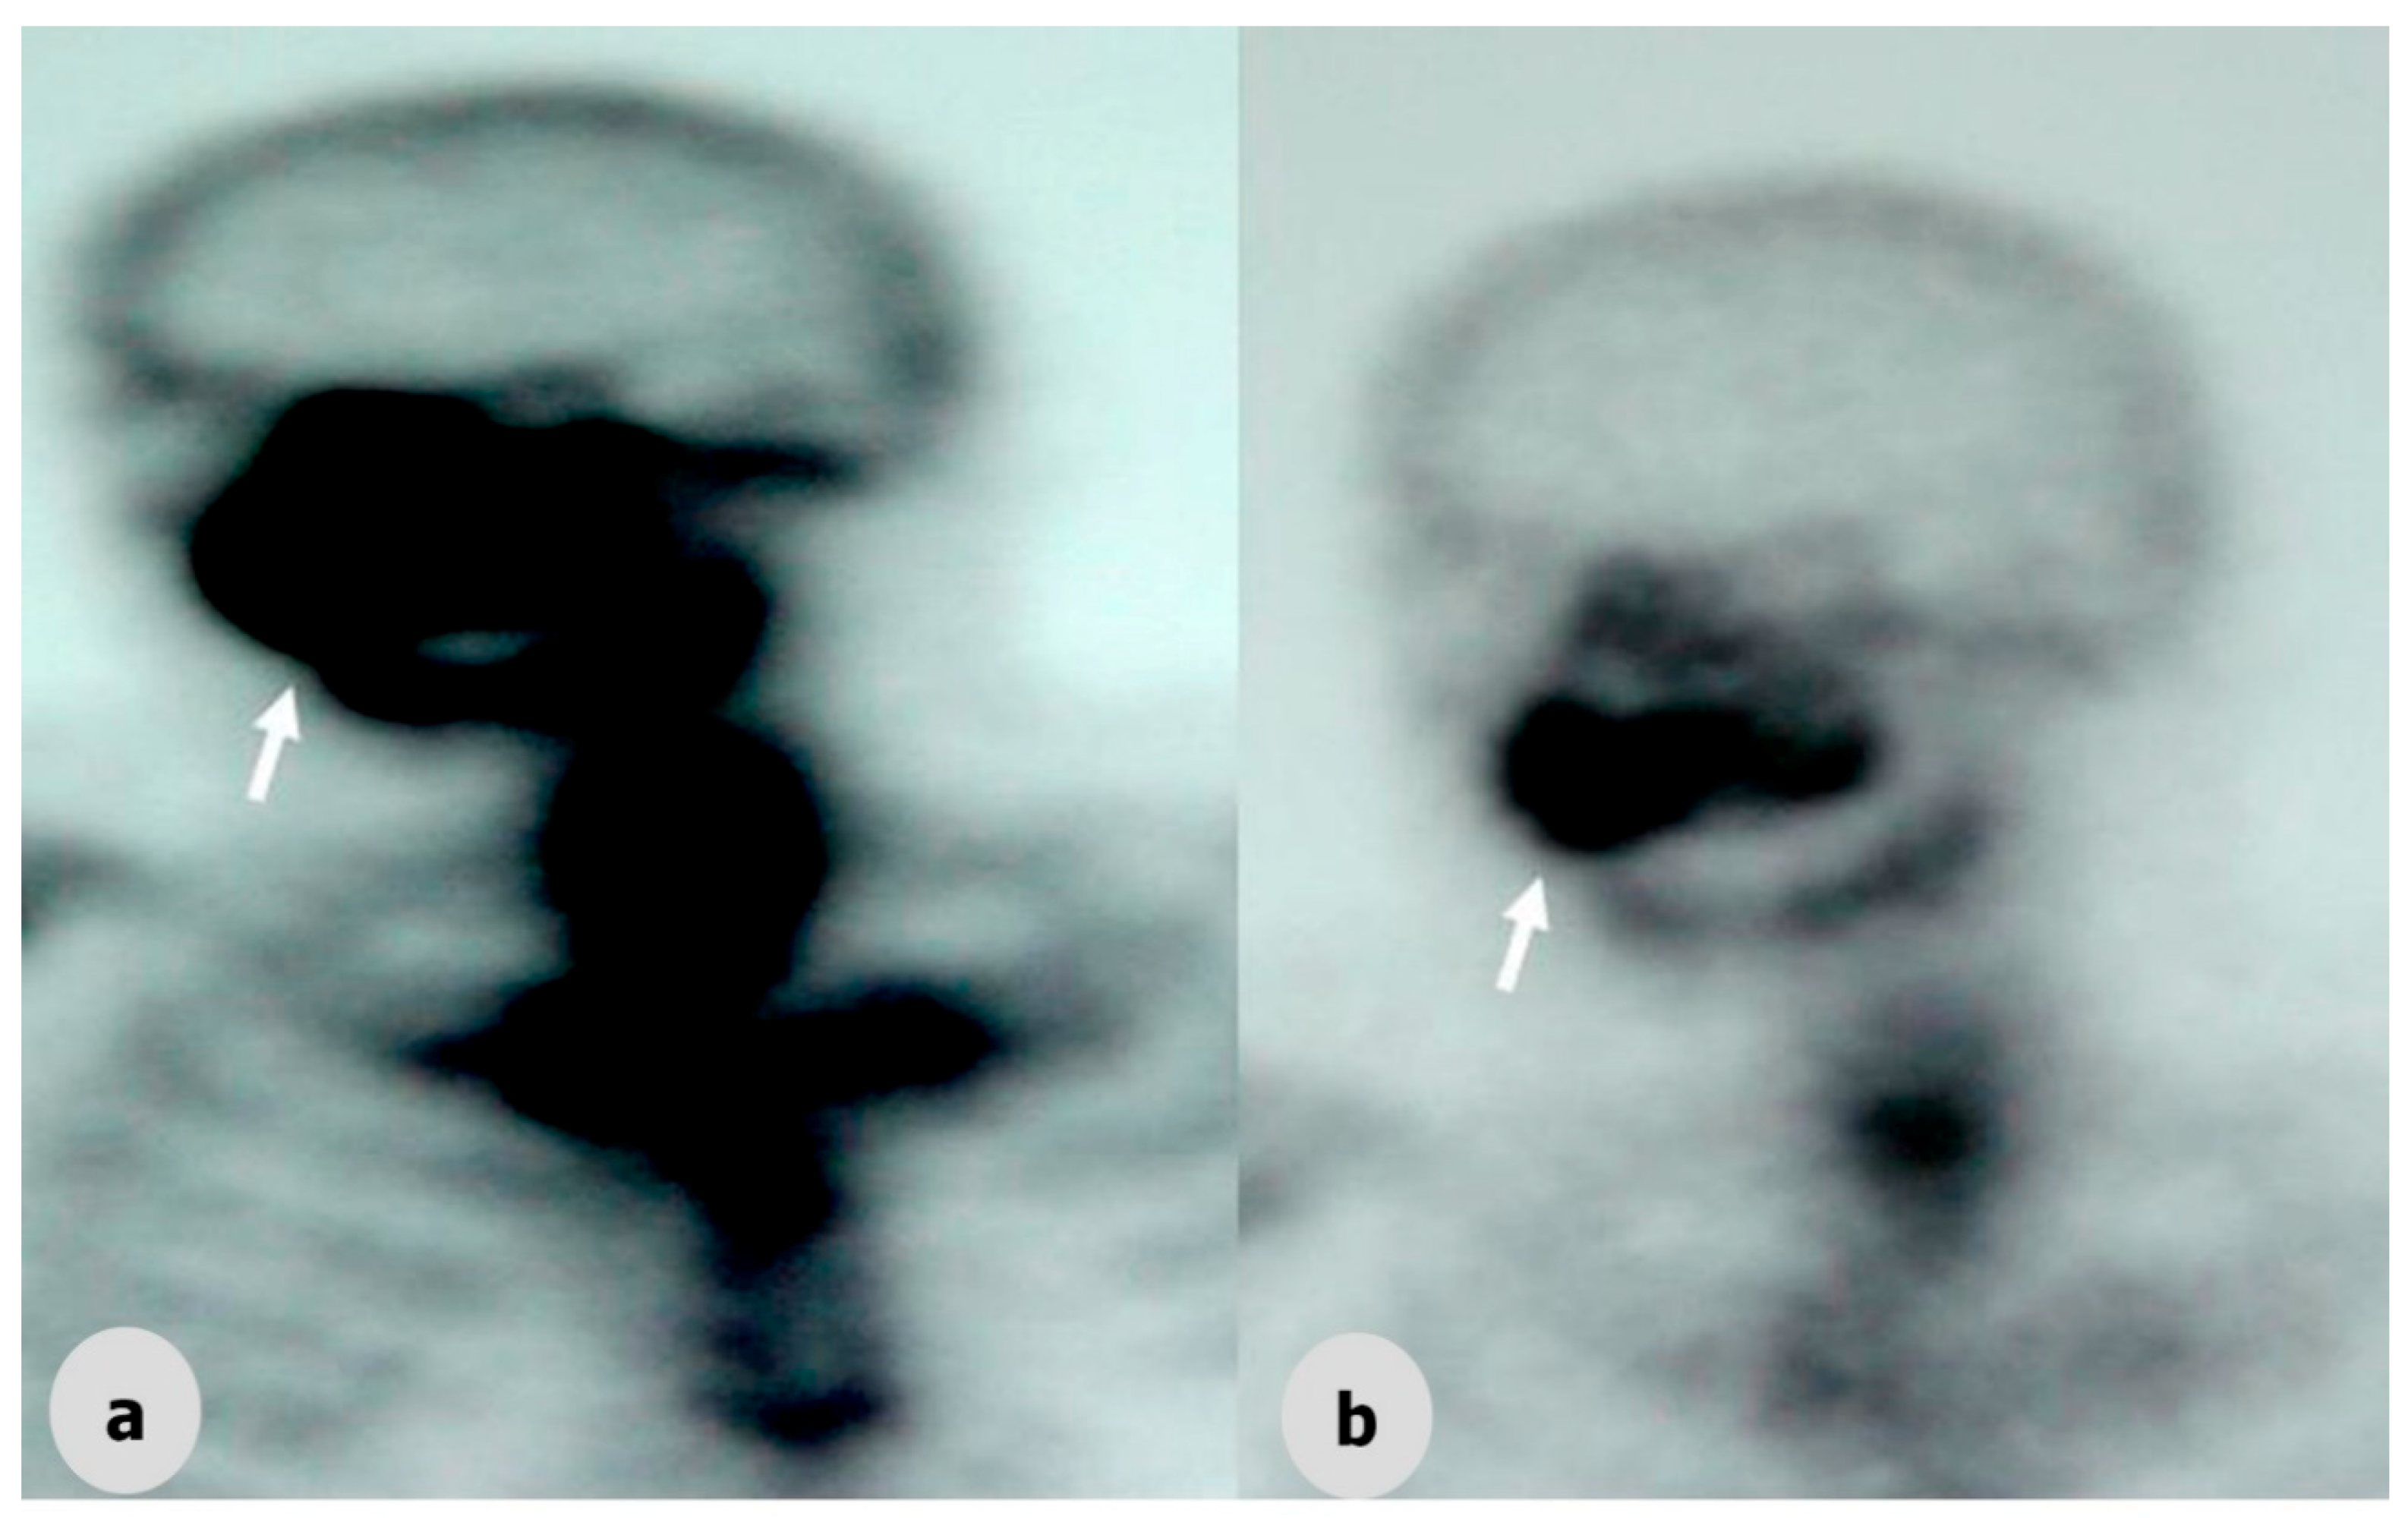

Before tumor resection, a dental impression was made using irreversible hydrocolloid impression material for fabrication of the immediate surgical obturator. Dental casts were fabricated with dental stone. The surgical limits were determined on casts with 3D tomography and MRI. The dental cast was cut from these boundaries. On the maxillary diagnostic cast, the surgical margins were plotted approximately whilst consulting with the surgical team because complete coverage of the surgical site with the obturator is crucial. Immediate obturators were prepared on these casts (Figure 3).

Figure 2. Axial and Coronal MRI weighted images showing a lesion of the maxillofacial region. (a1–3) MRI images of a palatomaxillar tumor on the horizontal plane before chemotherapy and radiotherapy (white arrows with red border); (b1–3) MRI images of the palatomaxillar tumor on the horizontal plane after chemotherapy and radiotherapy (white arrows with red border); (c) MRI images of the palatomaxillar tumor on the sagittal (c1,2) and frontal (c3) plane after chemotherapy and radiotherapy (white arrows with red border).